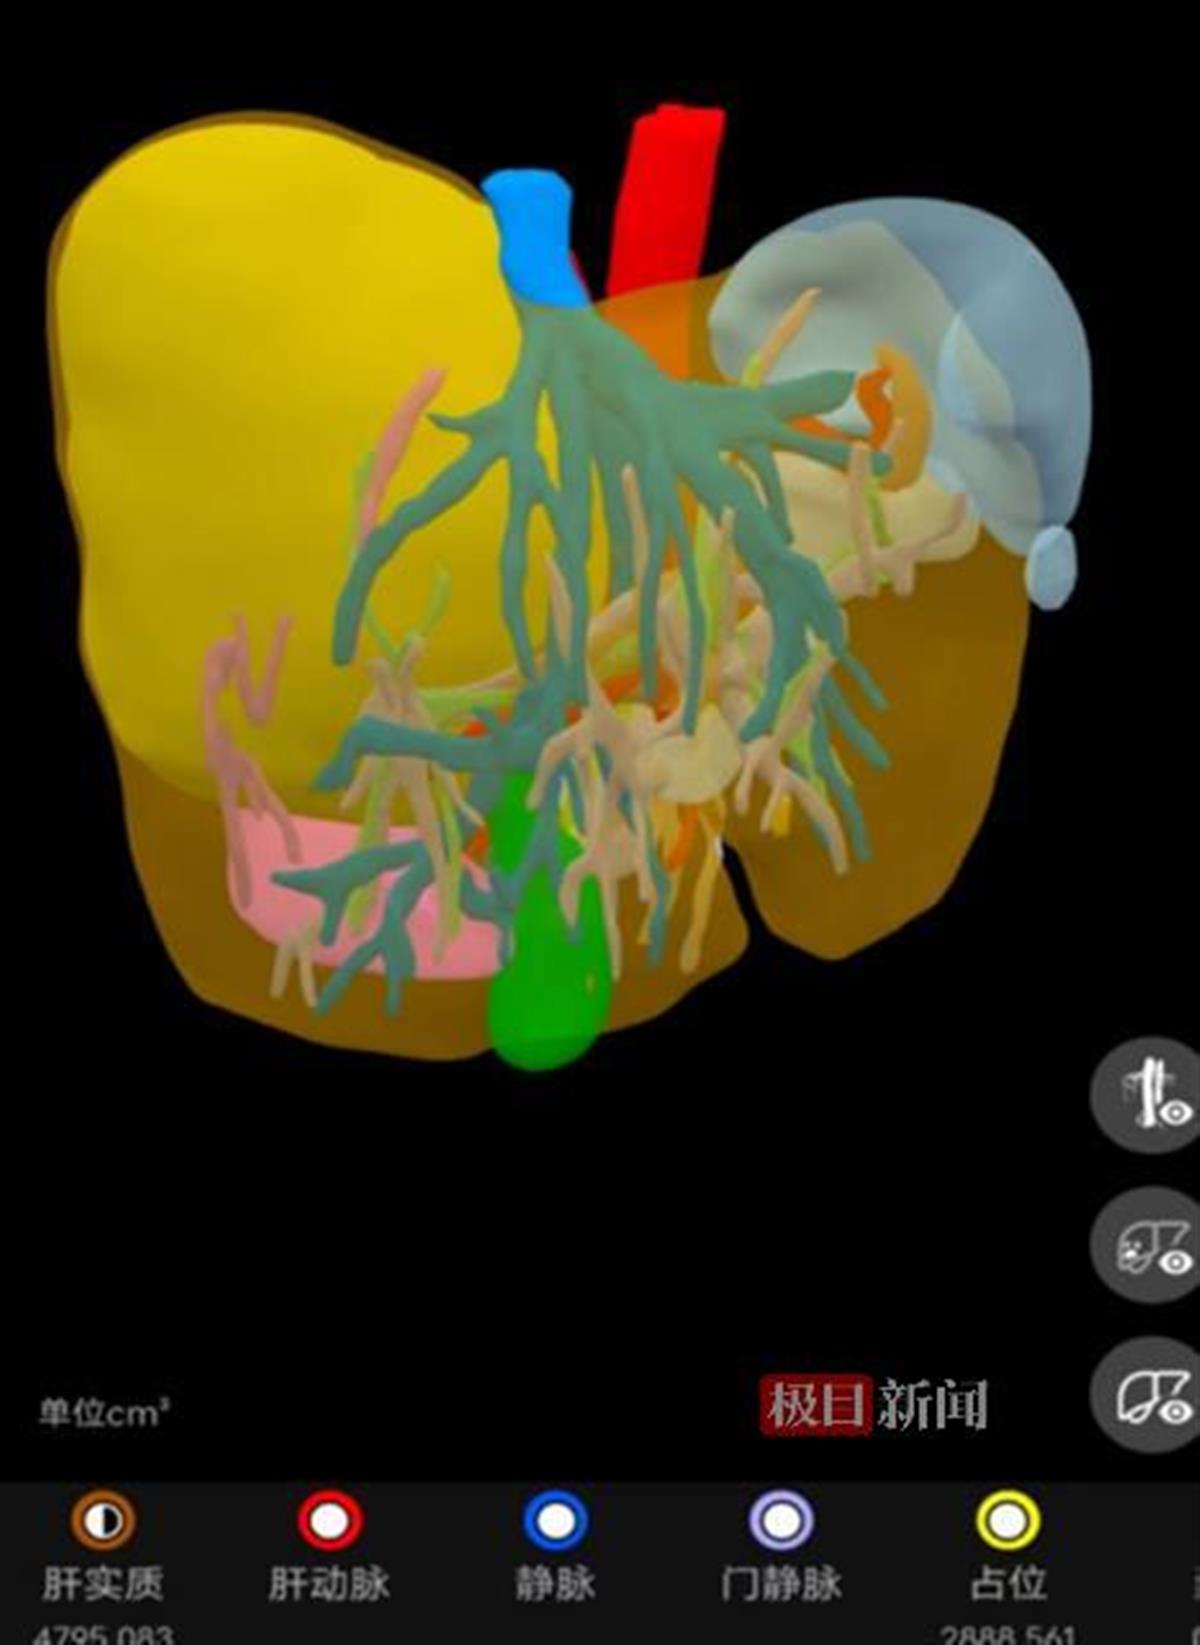

经过三维重建评估,患者的肝脏重约4795克,是正常肝脏的3倍多,其中肝脏肿瘤的重量约2888克,占了肝脏重量的一半以上。经过评估,患者肝脏上的病灶是单个的,且肿瘤呈膨胀性生长,从影像学上看有完整的包膜,属于早期肝癌,切除后效果会比较好。

三维重建影像,浅黄色部分为肝脏肿瘤